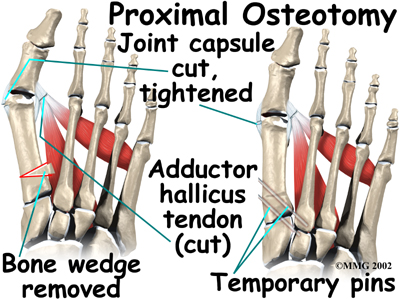

Proximal Osteotomy

In other situations, the first metatarsal is cut at the near end of the bone (called a proximal osteotomy.) This type of procedure usually requires two or three small incisions in the foot. Once the skin is opened the surgeon performs the osteotomy. The bone is then realigned and held in place with metal pins until it heals at which point the pins are removed. Again, this reduces the angle between the first and second metatarsal bones.

Realignment of the big toe is then done by releasing the tight structures on the lateral, or outer side of the first MTP joint. This includes the tight joint capsule and the tendon of the adductor hallucis muscle. This muscle tends to pull the big toe towards the middle of the foot. By releasing the tendon, the toe is no longer pulled out of alignment. The toe is realigned and the joint capsule on the side of the big toe closest to the other foot is tightened to keep the toe straight, or balanced.

Once the surgeon is satisfied that the toe is straight and well balanced, the skin incisions are closed with small stitches. A bulky bandage is applied to the foot before you are returned to the recovery room.